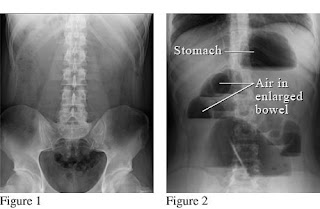

Adanya dilatasi dari usus disertai gambaran “step ladder” dan “air fluid level” pada foto polos abdomen dapat disimpulkan bahwa adanya suatu obstruksi. Foto polos abdomen mempunyai tingkat sensitivitas 66% pada obstruksi usus halus, sedangkan sensitivitas 84% pada obstruksi kolon.

Pada foto polos abdomen dapat ditemukan gambaran ”step ladder dan air fluid level” terutama pada obstruksi bagian distal. Pada kolon bisa saja tidak tampak gas. Jika terjadi stangulasi dan nekrosis, maka akan terlihat gambaran berupa hilangnya muosa yang reguler dan adanya gas dalam dinding usus. Udara bebas pada foto thoraks tegak menunjukkan adanya perforasi usus. Penggunaan kontras tidak dianjurkan karena dapat menyebabkan peritonitis akibat adanya perforasi.